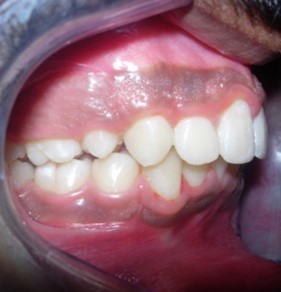

The soft tissue frontal and profile improved dramatically. (Figure 7a-b). The bilateral posterior crossbite was corrected. The severe increase in overjet of about 13mm was effectively reduced to 3mm and the severe deep bite was also corrected (Figure 7c,Figure 7d). Fixed maxillary and mandibular lingual retainers were given. (Figure 7e, Figure 7f). Post orthodontic treatment, normal root inclinations of the teeth and normal alveolar bone levels was observed. (Figure 8).

Figure 7d.Post treatment intra-oral – Right